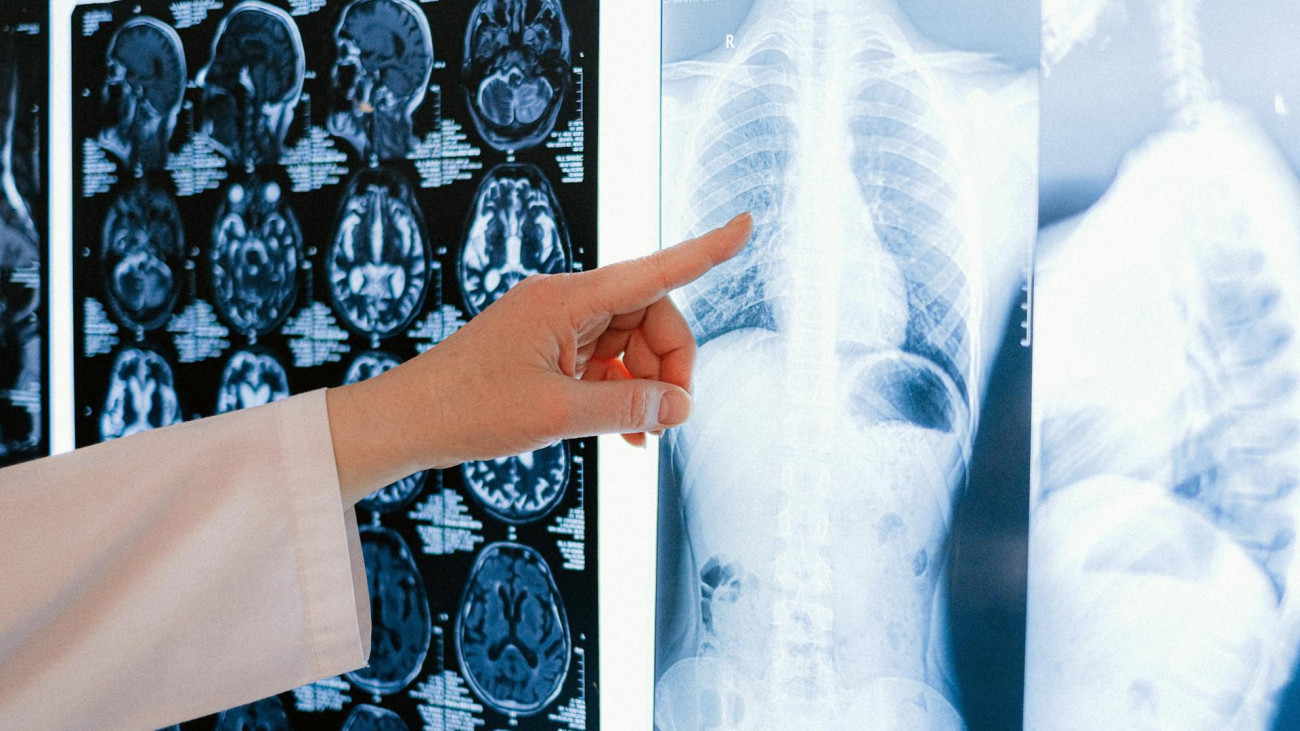

Milyen rákszűrésen ajánlott részt venni?

Mutatjuk, milyen rákszűréseken ajánlott részt venni!

Mellrák: nyolcból egy nőnél megjelenik a betegség, a szűrés életbevágó

Minden nyolc nőből egynél kialakul a mellrák.

Júniusban elfogadta az Országgyűlés azt a törvénymódosítást, mely szerint januártól bevezethetik a kötelező szűrővizsgálatokat. A törvénymódosítás következtében a méhnyakszűrés, az emlőszűrés, illetve a vastag- és végbélszűrés válik kötelezővé. Dr. Váradi Péter, a Prémium Egészségpénztár vezető stratégiai tanácsadója és Dr. Kincses Gyula egészségpolitikus, a Magyar Orvosi Kamara volt elnöke beszélt a Reggeliben arról, a magyar várható élettartam hogyan helyezkedik el a világban, hogyan gondolkodunk az egészségünk iránti felelősségről, mit hozna magával a kötelező szűrővizsgálat, és mekkora a munkáltatók szerepe az egészségügyi felelősségben. Dr. Kirschner András orvossal pedig arról beszélgettünk, melyek azok a vizsgálatok, amelyek a legfontosabbak lennének mindenki számára.

Mivel Magyarországon rendkívül sokan halnak meg idő előtt rákban, nem ördögtől való a daganatos betegségek felismerését szolgáló szűrővizsgálatok kötelezővé tétele. Viszont ahhoz, hogy ez bármit is érjen, sürgősen rendbe kéne tenni az egészségügyet.

Lesújtó eredményre jutott egy magyarországi kutatás, amely szerint a lakosság fele egyáltalán nem törődik azzal, hogy a rák kockázatát rendszeres szűrővizsgálatokkal mérsékelje, holott ez lenne az egyik leghatékonyabb módja a megelőzésnek. Valójában csak néhány területen kellene sokkal fegyelmezettebbnek lennünk ahhoz, hogy jó eséllyel elébe tudjunk menni a daganatoknak, valamiért mégsem vagyunk ennyire összeszedettek.